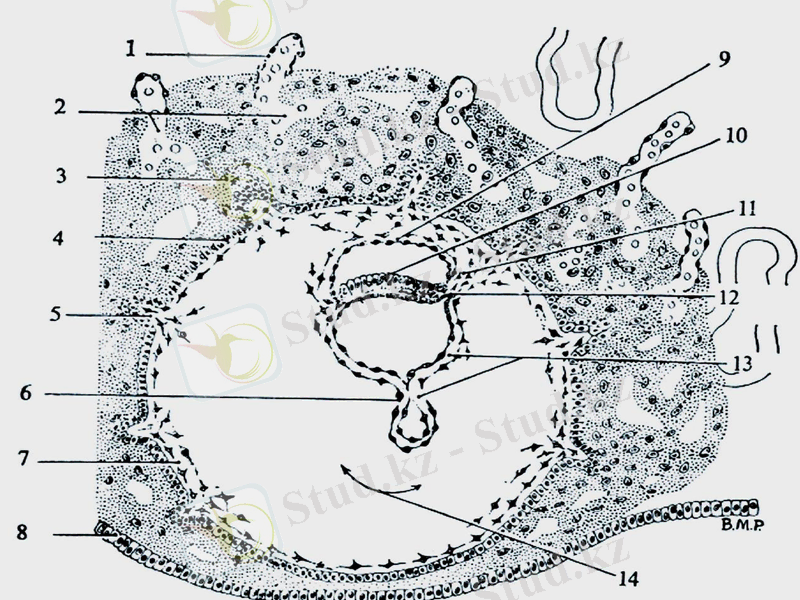

6. Гаструляция

ҰРЫҚТАН ТЫС МҮШЕЛЕРІ

ЖОСПАР

1. Хорион

2. Амнион

3. Сары уыз қабы

4. Аллантоис

5. Кіндік жібі

6. Плацента

7. «Ана - нәресте» жүйесі